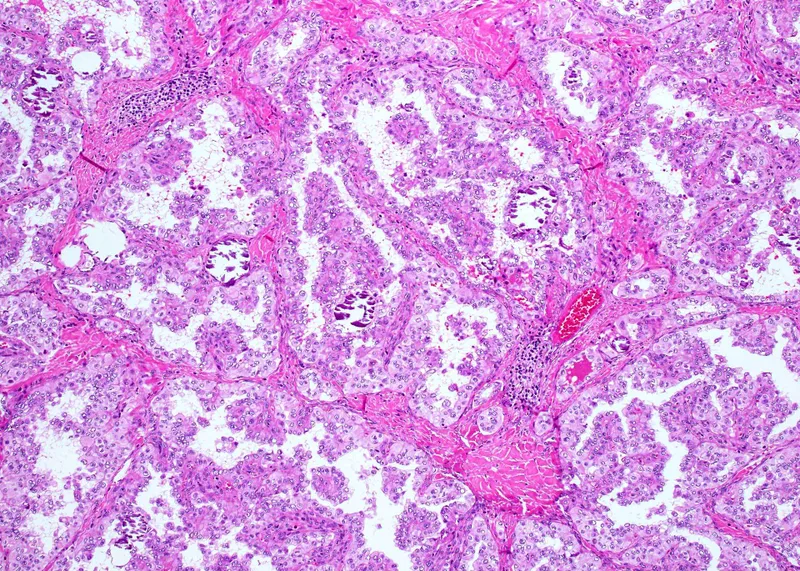

Cytological Interpretation - Decoding the Cells

- General Cytomorphological Features:

- Background: Clean, bloody, inflammatory, necrotic

- Arrangement: Clusters, sheets, acini, papillary, single cells

- Cell: Size, shape

- Nucleus: N:C ratio, chromatin (fine/coarse), membrane (smooth/irregular), nucleoli (inconspicuous/prominent)

- Cytoplasm: Amount, color, granules, vacuoles, inclusions

⭐ Accurate interpretation requires assessing both individual cell morphology and the overall architectural pattern of cell groups, alongside clinical context.